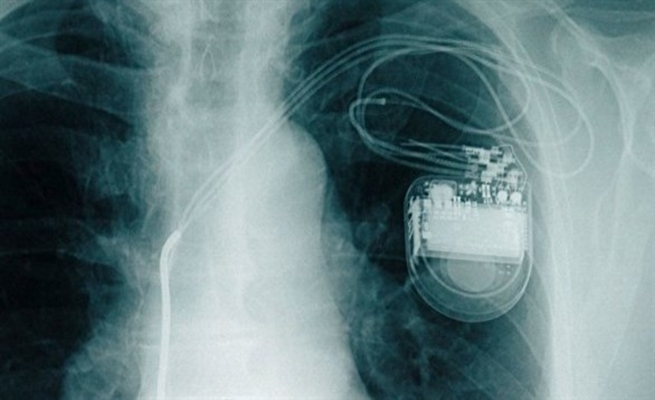

الأجهزة الإلكترونية قد تؤثر بالسلب على منظم ضربات القلب

حذرت الجمعية النمساوية لطب القلب من أن الأجهزة الإلكترونية قد تؤثر بالسلب على وظيفة منظم ضربات القلب؛ حيث يمكن أن يحدث اضطراب بسيط في ضربات القلب أو قد يصل الأمر إلى حد فقدان الوعي.